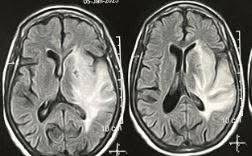

كما تم إنقاذ شاب يبلغ من العمر 15 عامًا بعد تعرضه لحادث سير أدى إلى نزيف حاد وكسور بالجمجمة. أُجريت له عملية جراحية عاجلة لتفريغ النزيف، مما ساهم في إنقاذ حياته.